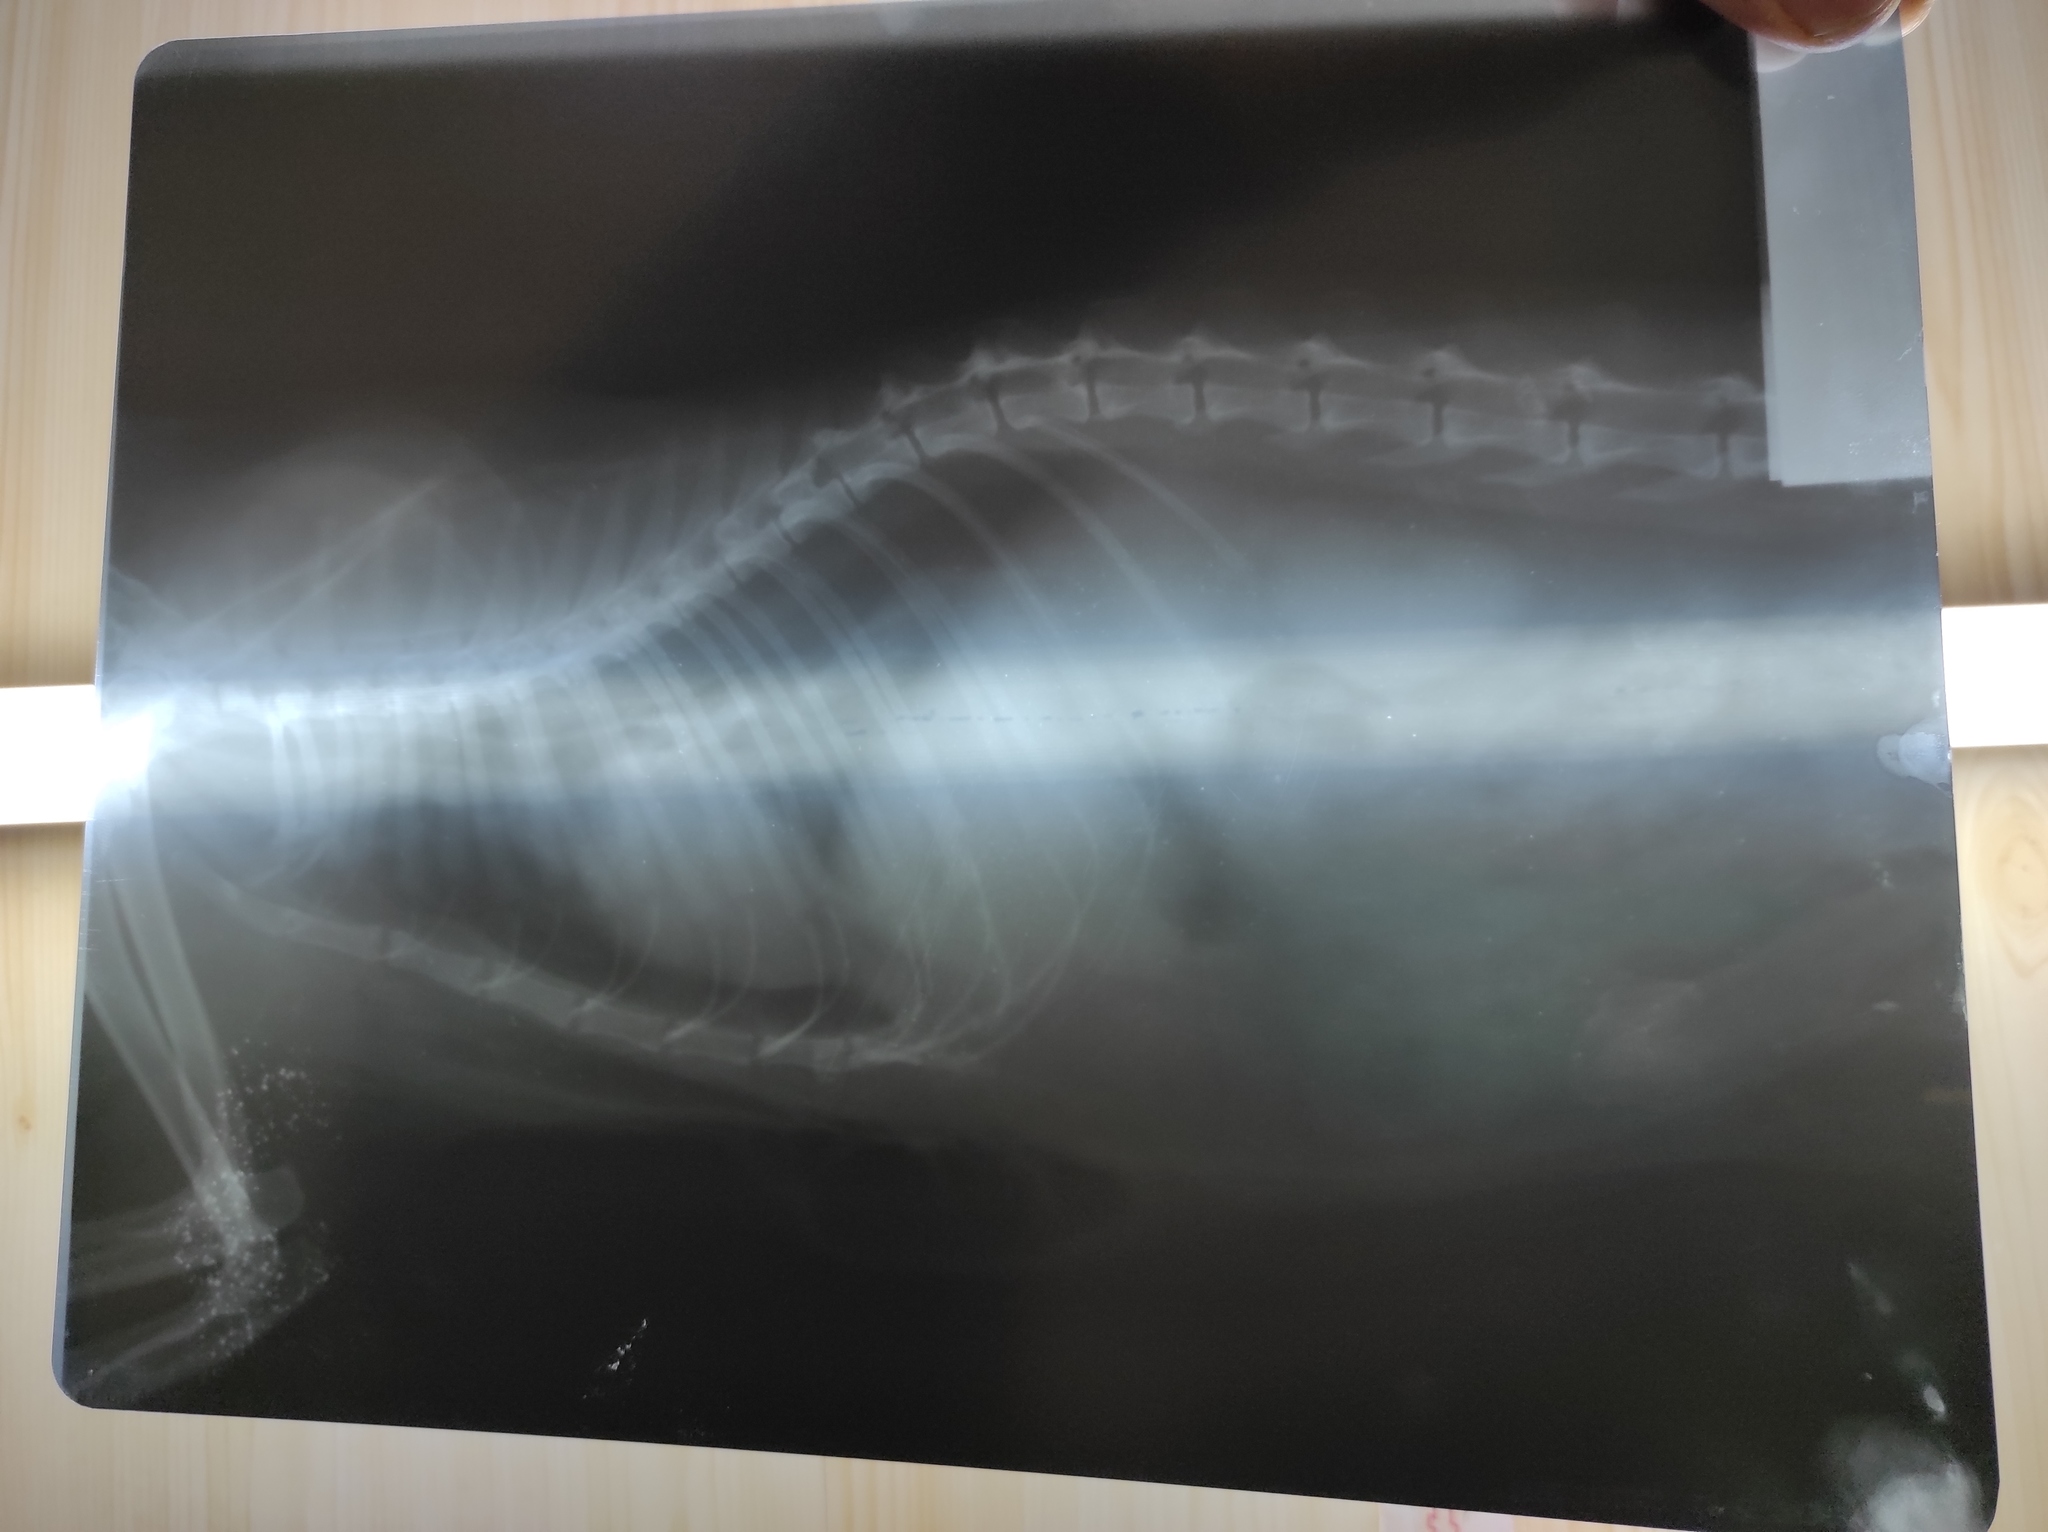

Только приехали от врачей. Помогал весь коллектив клиники. На рентгене видна гематома в месте удара, на животе синяк. Сломаны хрящи рëберные, немного воздуха под кожу вышло. Сделали тугую повязку, поставили уколы. Клетку для кроликов уже заказали, будет в ней жить ближайшее время. Состояние стабильное, прогнозы хорошие, а дальше видно будет.